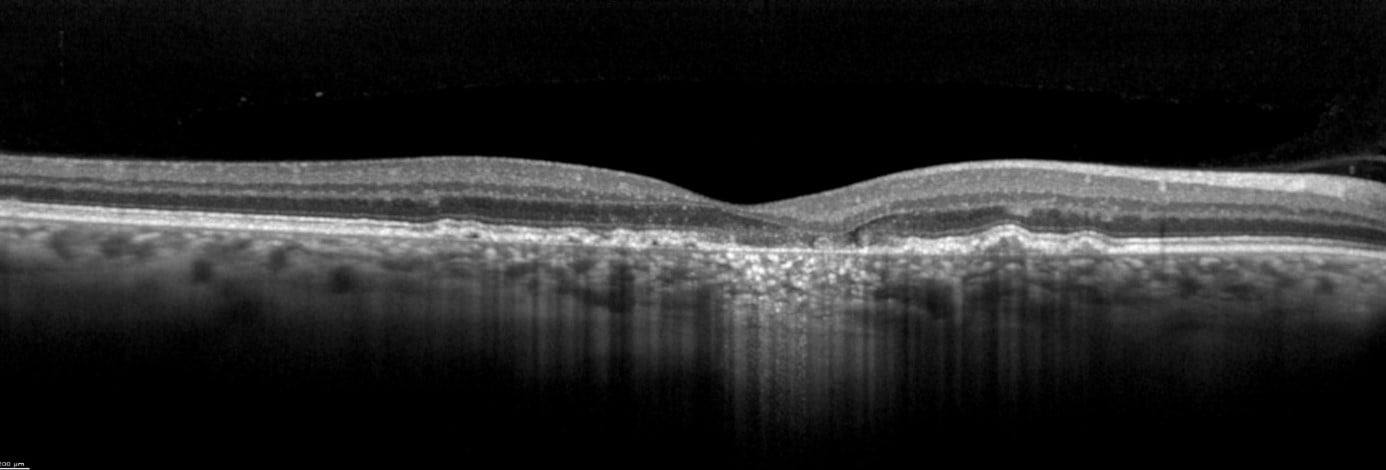

The vitality of the RPE is not the only factor of importance in GA. One of the advantages of OCT imaging is the three-dimensional cross-sectional imaging, which allows detailed viewing of fine structures. Individual retinal layers can be visualized to assess the RPE and photoreceptors. OCT is also a useful method to examine areas surrounding atrophy, such as discontinuous outer bands (external limiting membrane, ellipsoid zone, and RPE, as well as "outer retinal tubulations" (ORT)). In addition to fundoscopy and fluorescein angiography, high-resolution SD-OCT should primarily be used for diagnosis and follow-up of active choroidal neovascularization (CNV). according to professional associations.

Image 2: SPECTRALIS high-resolution OCT image courtesy of Dr. Rosa Dolz-Marco, Valencia, Spain

The transverse section or en-face OCT image option provides a unique visualization of RPE and photoreceptor structure, adding complementary information relating to the distribution of pathological change within the posterior segment. One characteristic of GA is choroidal hypertransmission defects, a “window” defect through the RPE associated with nascent GA (nGA) and cRORA, providing a complementary alternative to autofluorescence images.

Image 3: Transverse section OCT – choroidal hypertransmission defect recorded with SPECTRALIS